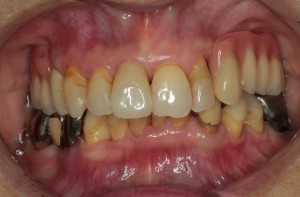

症例⑤

上左右の奥歯を失ってしまったため、保険の入れ歯を入れたが、違和感が強く、しっかり噛むことができないため、インプラントを併用した入れ歯を作ることで違和感なく、しっかり噛むことができるようになった。 また通常の入れ歯は、はずれないようにするため金属のバネを歯に引っ掛けるため見た目も悪いが、インプラントによって固定されているためバネもなく、見た目も非常に良いものとなっている。

術前